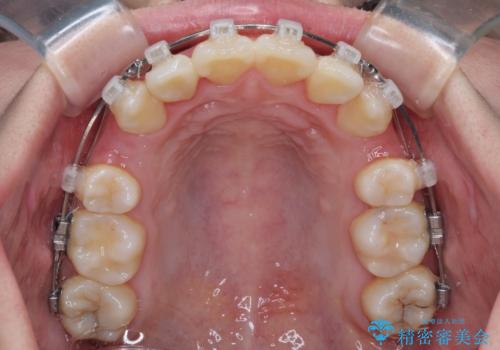

- クリアブラケット

口元を積極的に引っ込めるために、上下左右の小臼歯計4本を抜歯することとしました。

舌の突出癖が強いため、しっかりと口元を引っ込めるため、舌のトレーニングをしっかりと行いながら矯正治療を行うこととしました。

下顎前歯の歯肉が元々薄く、歯肉退縮リスクがあったため、細心の注意を払って治療を進めましたが、残念ながら1歯退縮を起こして歯根が露出してしまいました。

今後、患者様と相談しながら、歯肉移植を行っていく予定です。